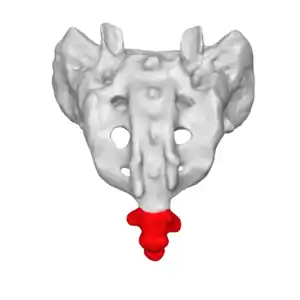

The location of the coccyx (in red) at the lower aspect of the sacrum of the pelvis